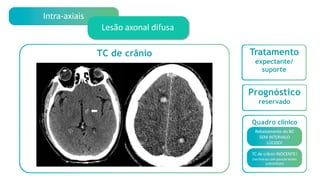

Intra-axiais

Lesão axonal difusa

Quadro clínico

Rebaixamento do NC

SEM INTERVALO LÚCIDO!

TC de crânio INOCENTE!

(normal ou com poucas lesões

Tratamento

expectante/

Prognóstico

reservado